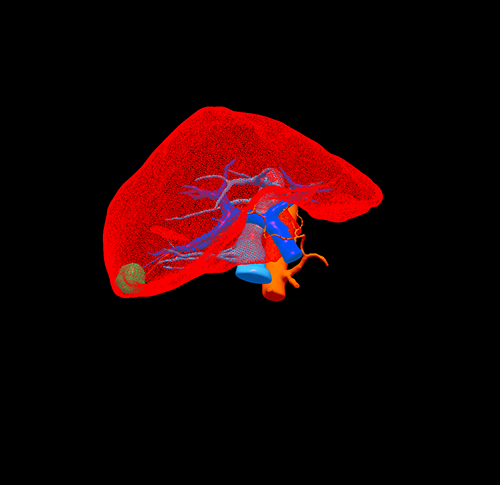

三维重建

S6肝癌-腹腔镜S6切除